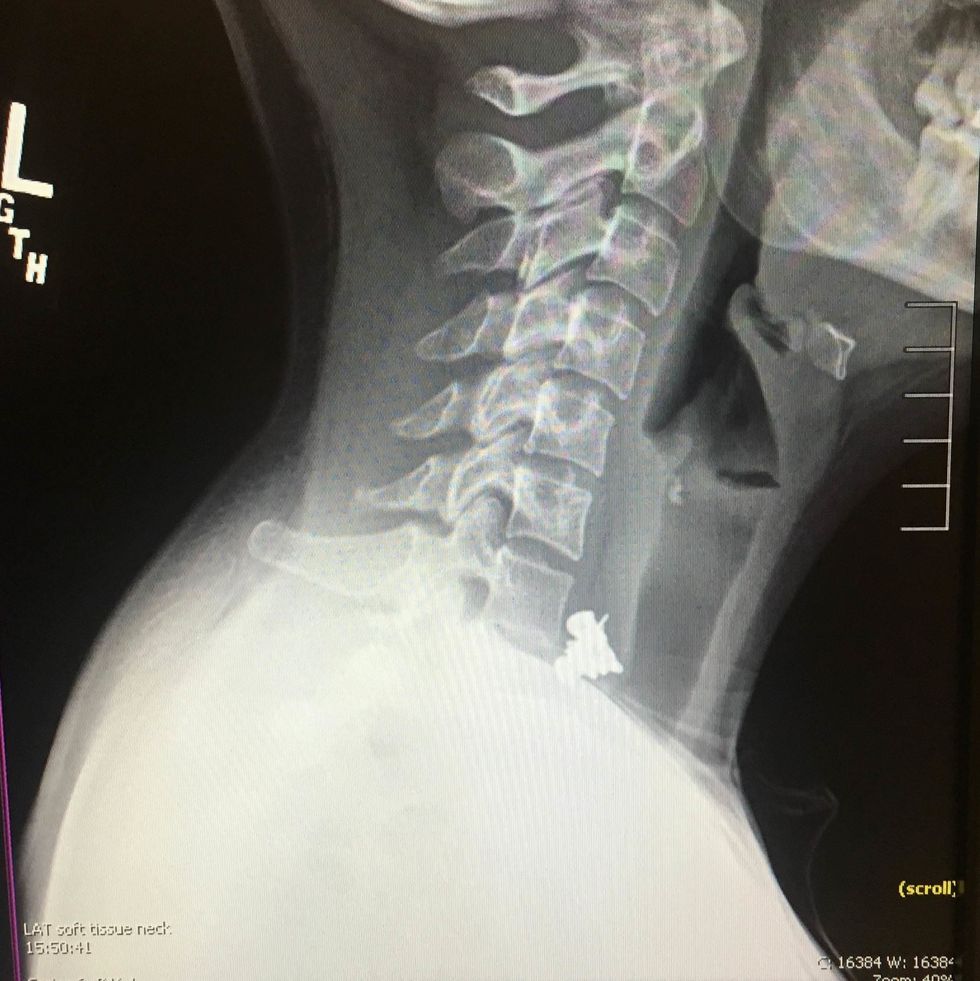

Emdarko then offered up even more X-rays and photos from before and DURING her operation: